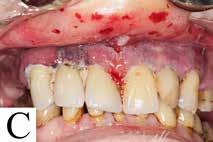

Behandling af MRONJ kan enten være konservativ eller kirurgisk. Konservativ behandling inkluderer bl.a. klorhexidinmundskyl og antibiotikum ved akutte infektioner. Den kirurgiske behandling afhænger af omfanget af MRONJ. Det er i litteraturen omdiskuteret, hvilke patienter der bør behandles konservativt og kirurgisk (1,3,9). På Afdeling for Kæbekirurgi, Rigshospitalet, er behandlingen af patienterne med MRONJ overvejende kirurgisk (Fig. 1).

Den sidste artikel er en kasuistik, hvor en 72årig mand henvises fra egen tandlæge til Rigshospitalets kæbekirurgiske afdeling med en slimhindeforandring på margo gingivae, som blev angivet til at være fire uger gammel. Det viste sig at være et planocellulært karcinom. I Tandlægebladet 2023, nr. 10 omtaltes i en oversigtsartikel planocellulært karcinom. Denne maligne tilstand kan udvikle sig hurtigt, hvorfor det er vigtigt straks at henvise til et pakkeforløb i ørenæsehalsregi. For denne patient var karcinomet hurtigtvoksende, og det endte med, at patienten skulle behandles med stråleterapi. Et lærerigt tilfælde.♦